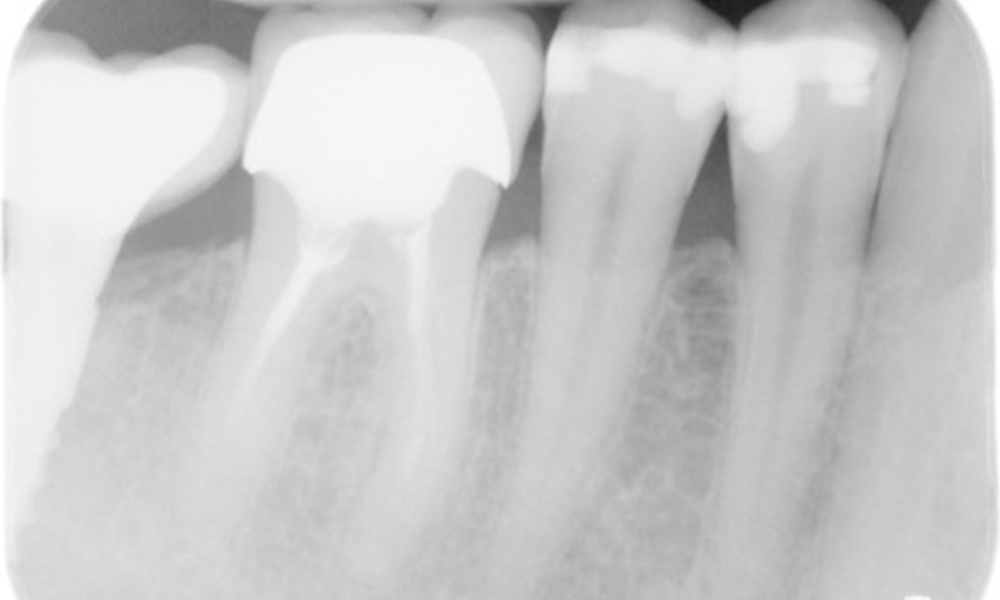

Рентгеновата снимка показва загуба на кост

Рентгенова снимка (или рентгенова снимка на захапката)

Рентгенова снимка (или рентгенова снимка на захапката), заснета на: 18/02/2021